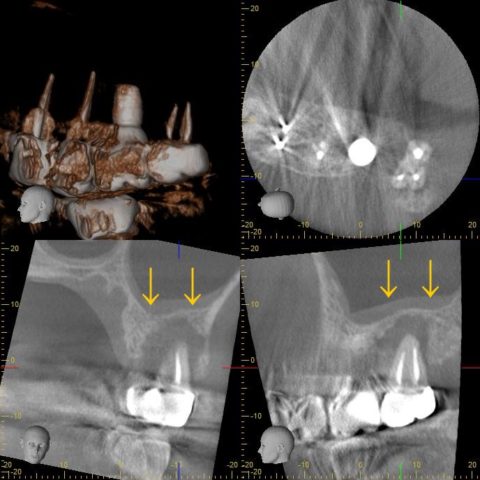

この方は左上の1番奥の歯を、自費で根管治療を行い、合わせて手前にはインプラントを入れたそうです。

お口全体のレントゲンとCTを診てもらうと、歯を支えている骨がゴッソリ溶けていました、、、

ここまで溶けているともう抜歯しか選択肢はありません😨